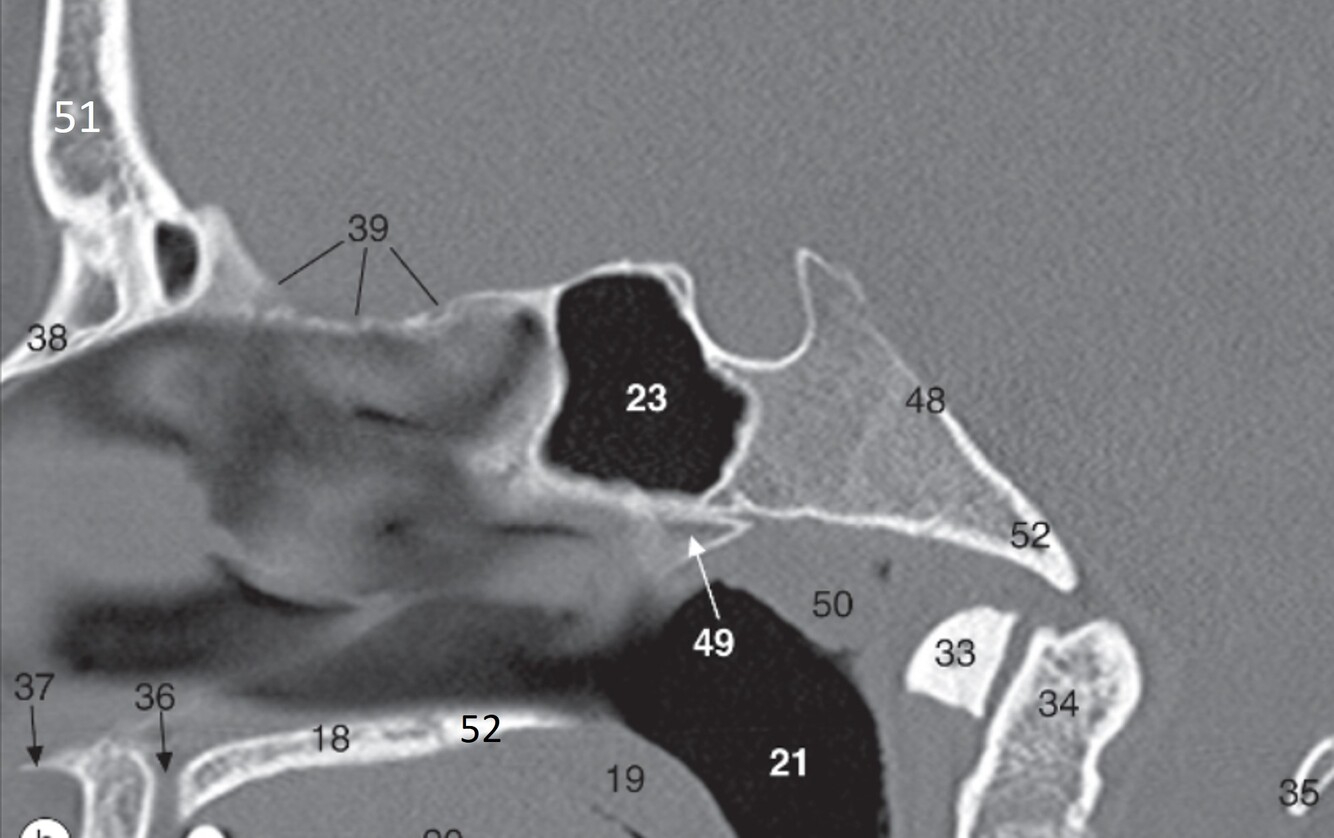

15

Label 18,19,21,23,33,34

18=Palatine process (Maxilla)

19=Soft palate

21=Nasopharynx

23=Sphenoid sinus

33=Anterior arch (C1)

34=Odontoid process (C2)

16

Label 35,37,38,39,48

35=Posterior arch (C1)

37=Acanthion

38=Nasal bone

39=Cribriform plate (Ethmoid)

48=Clivus

17

Label 49-52

49=Vomer

50=Pharyngeal tonsils

51=Frontal bone

52=Horizontal plate (palatine bone